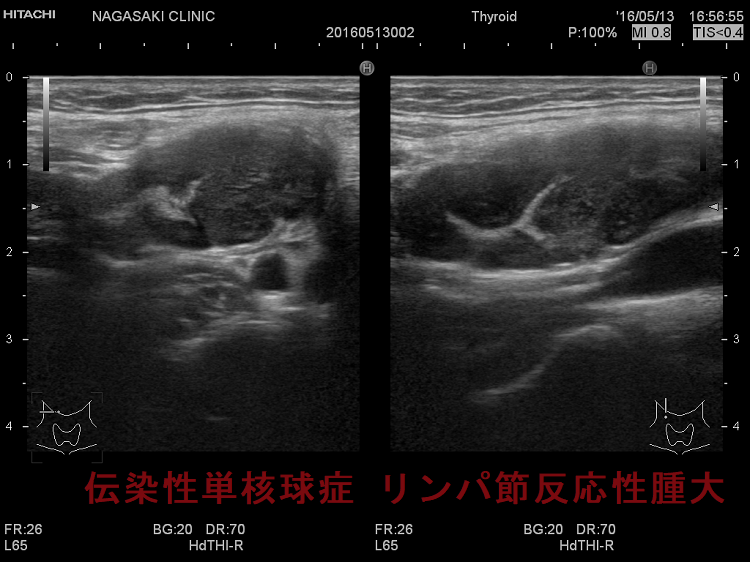

亜急性甲状腺炎と鑑別を要する伝染性単核球症。喉(のど)の痛みと首のリンパ節の腫れを甲状腺の病気と思って、長崎甲状腺クリニック(大阪)を受診される方がおられます。

- 痛みを伴う著明な後頸部リンパ節腫脹は1〜2週頃がピークで、耳下腺の下、外側頚部まで累々と広がり、全身のリンパ節も腫大します。

- 亜急性甲状腺炎と鑑別を要する伝染性単核球症を発症